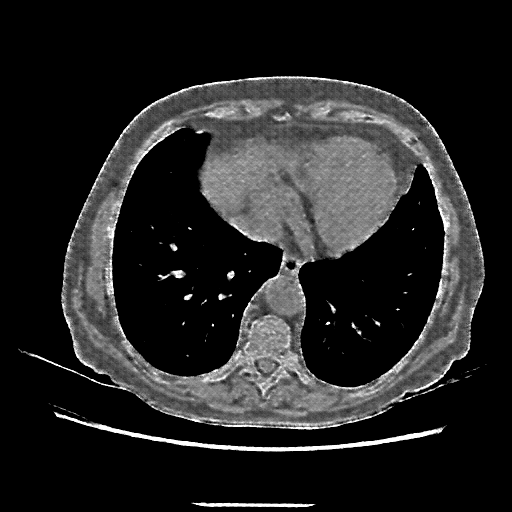

Original VENOUS CT scan

Full window (WL 1023.5, WW 4095 β†’ Low βˆ’1024, High +3071)

Mediastinum window (WL 40, WW 400 β†’ Low βˆ’160, High +240)